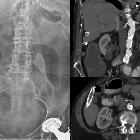

abgerissener Drainageschlauch

Fremdkörper Radiopaedia • CC-by-nc-sa 3.0 • de

CT

The density of the foreign material in the body can range markedly, so the use of multiple window settings is crucial in identifying the presence of the objects. Routinely soft tissue, lung, and bone windows should be assessed. Certain plastics may be occult on CT.

Assoziationen und Differentialdiagnosen zu abgerissener Drainageschlauch: